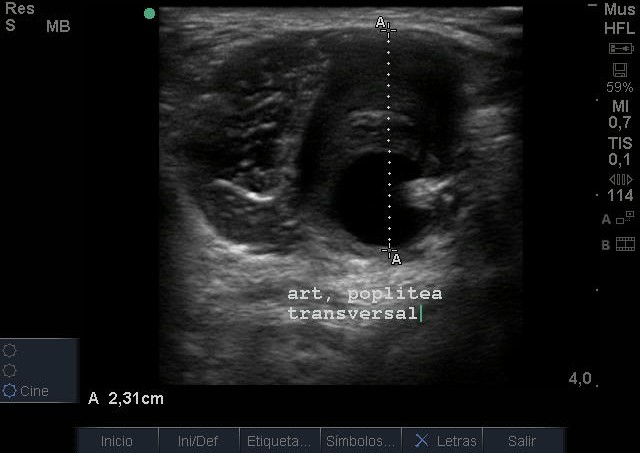

Se visualiza aneurisma de 2 centímetros con imagen compatible con trombo intramural. En modo Doppler flujo turbulento. Realizamos ecografía de rodilla contralateral y aórtica sin hallazgos reseñables.

Juicio Clínico: Aneurisma poplíteo con trombo intramural.